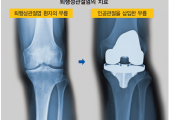

[백세시대] 계단 내려가다 주저앉게 되면 퇴행성관절염 의심

퇴행성관절염의 원인과 치료노화·비만 등이 퇴행성 변화 불러… 방사선 검사만으로도 진단 가능초기는 약물·주사제로 치료… 말기..